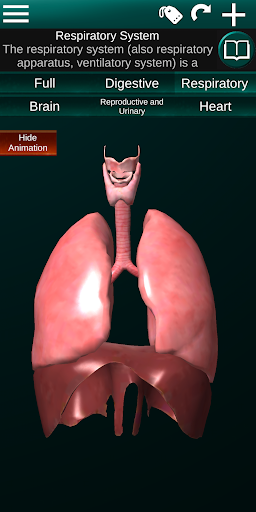

* Sistem pernafasan, yang meliputi trakea, bronkus, paru-paru dan animasi sistem ini.